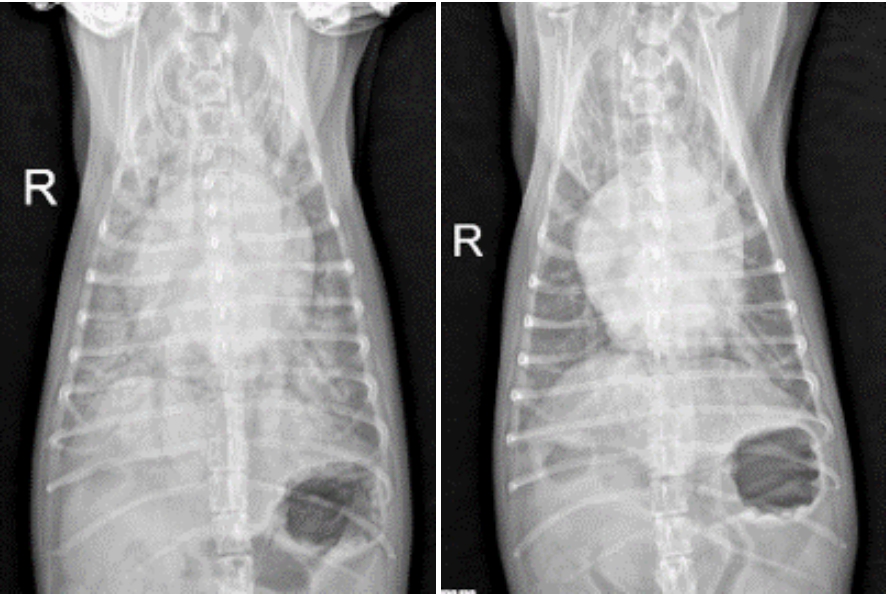

흉부 방사선 촬영(X-ray)

심비대, 폐부종 (Cardiomegaly, Cardiogenic Pulmonary Edema)

방사선 촬영 결과,

VHS (Vertebral Heart Score)는 12.3, VLAS (Vertebral Left Atrial Size)는 3.0으로 확인되었습니다.

흉부 방사선 촬영상 심장은 정상보다 매우 커져 있었으며, 특히 좌심방이 확장되어 있는 상태임을 의미합니다.

또한 폐 전체에 걸쳐 심한 간질–폐포 패턴이 확인되었는데, 이는 폐에 액체가 차 있는 폐부종(CPE, cardiogenic pulmonary edema) 의

전형적인 방사선 소견입니다.

아이의 경우 심장 기능 저하로 인해 폐에 물이 차면서 숨 쉬는 것이 매우 어려운 상태였고, 이로 인해 위급한 호흡곤란이 발생한 것으로 판단되었습니다. ▼

방사선 검사상 폐에 고여 있던 물(침윤)도 점차 흡수되며 개선되는 소견을 보였고, 이에 따라 승압제는 중단하였으며 이뇨제와 정맥확장제는 점차 감량하기 시작했습니다. ▼

내원 당시(좌), 입원 1일차 (우)